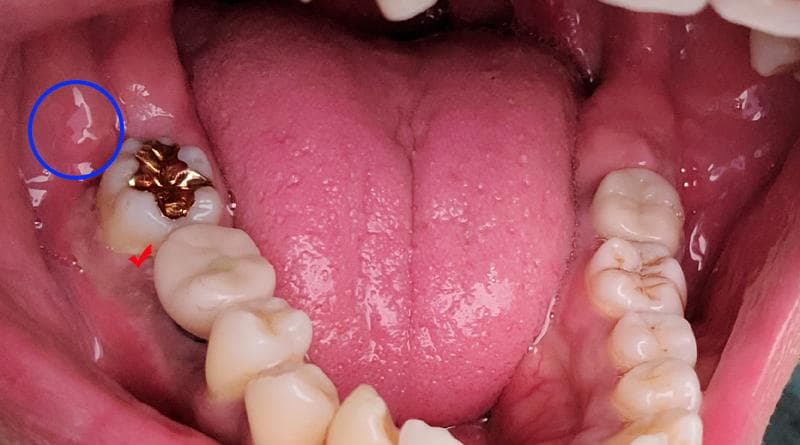

8/25일 통증이 생겼고 처음에 사진상 빨간 체크부위가 아파서 내원했습니다. 이후 9월1일부터 지금까지 잇몸치료(미노클린주입) 2회 -> 임플란트 상부보철물제거 -> 9월20일 인레이치아 부터 뒤쪽 잇몸까지 절개 소파술 시행 하였습니다. 현재는 저 부위에 통증은 사라진 상태지만 통증이 이동하여 파란동그라미 부위에 통증이 생겨 현재도 약을 복용하고 있습니다. 큰통증은 잡혔지만 아직도 통증의 원인을 모르겠습니다.

대학병원 치주과에서도 엑스레이 초진에선 이상없다고 하셔서 추후 10월16일 다시 가보기로 했는데, 혹시 비치성치통은 아닌지 신경적인 문제인지 잘모르겠습니다. 고칠 수 없는건 아닐지 불안하고 답답하네요.

치아로 인해서 점막조직이 자극이 되면 사진처럼 보이며 불편감을 유발할수 있습니다 점막을 자극하지 않기 위해서는 치아에 힘을 적게 주어 점막조직이 치아 사이에 밀려나지 않게 해보는것이 도움이 될수 있습니다.